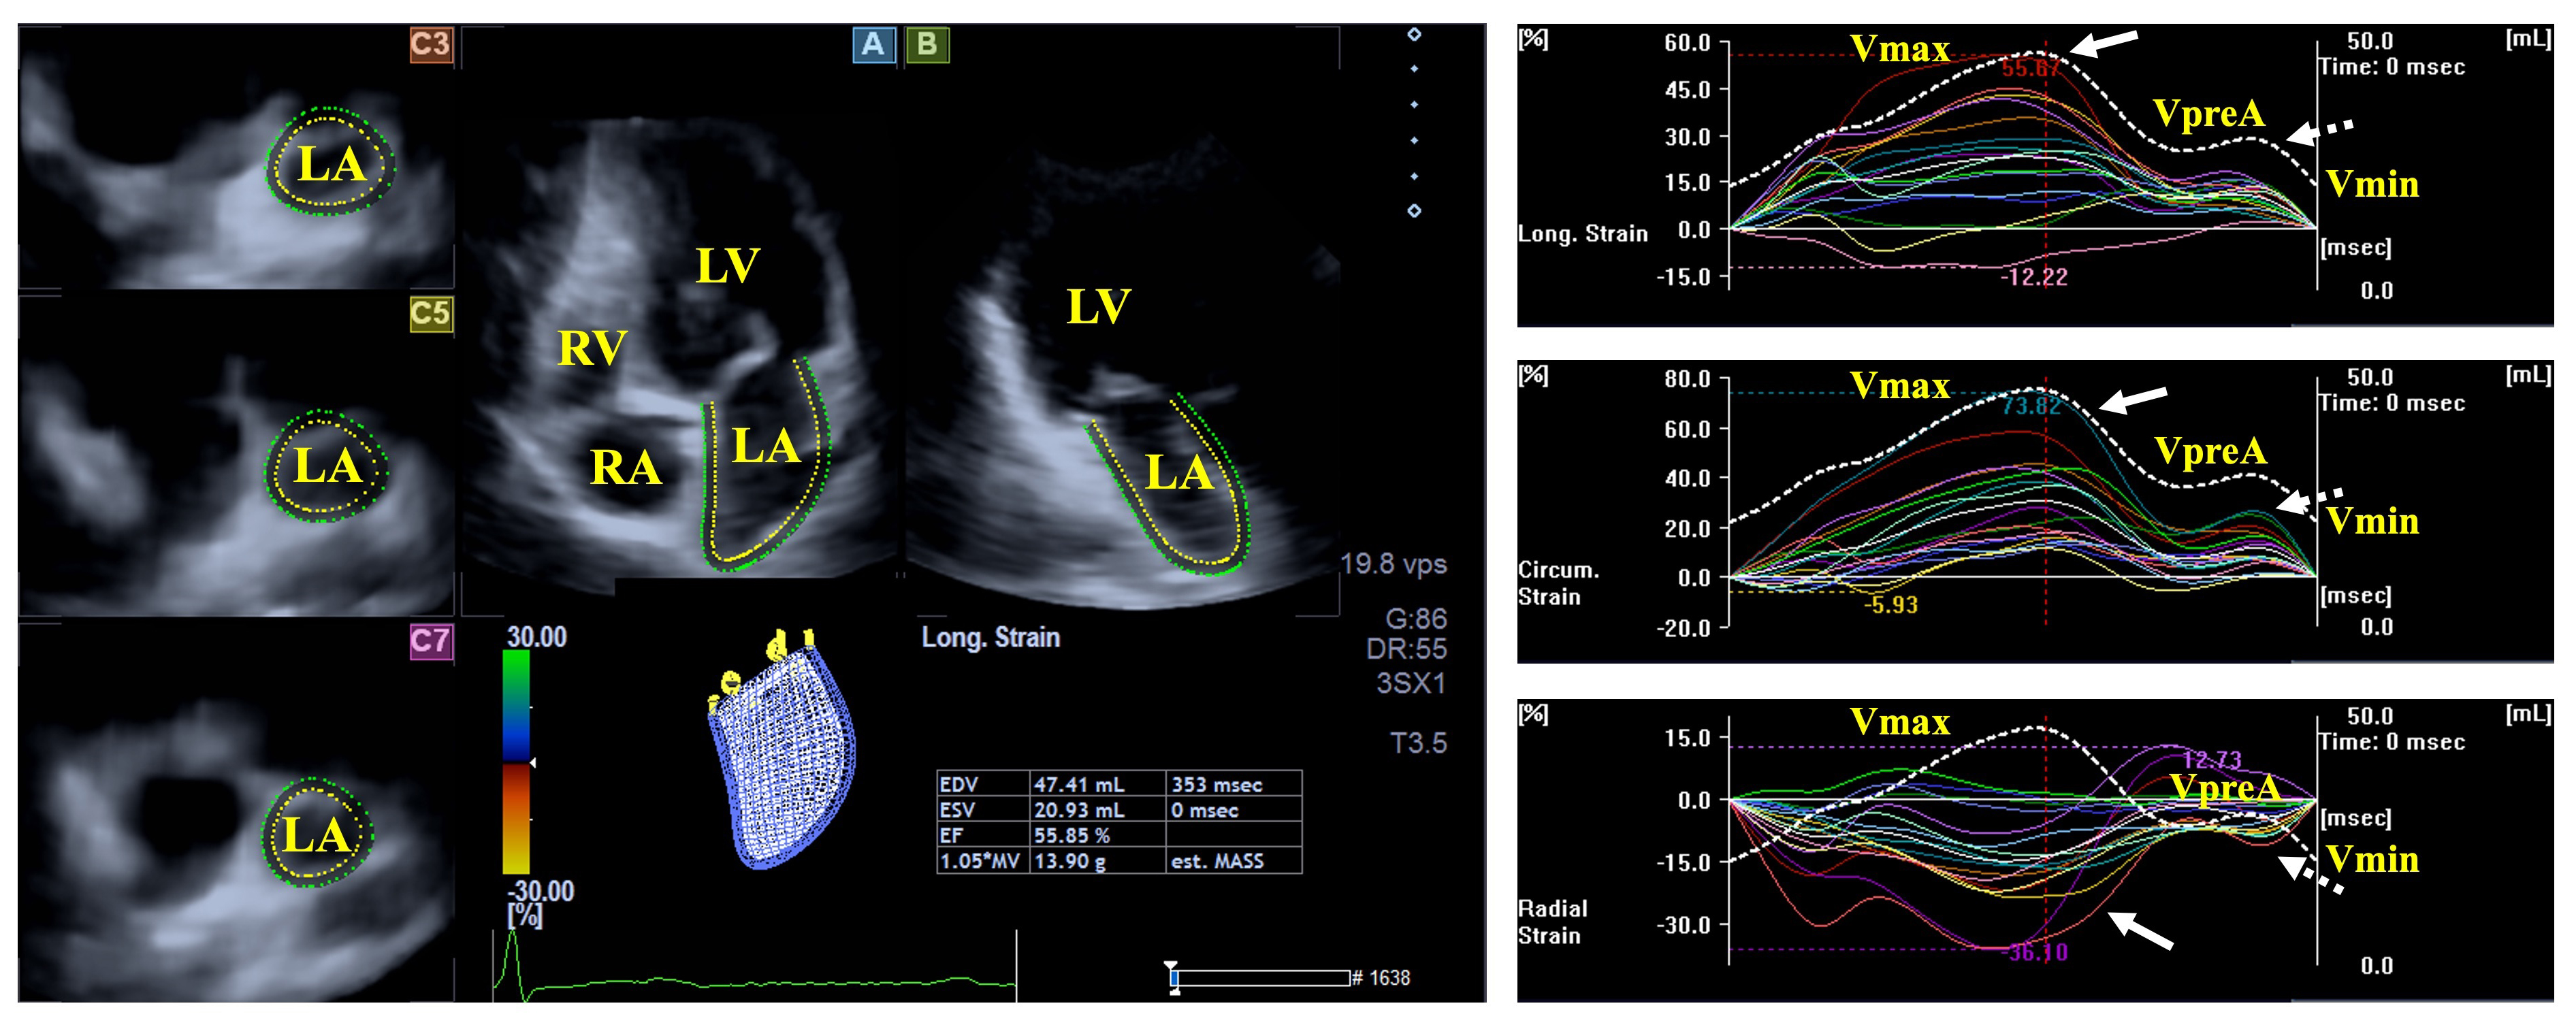

The LA fills from the four pulmonary veins and empties into the LV via the mitral apparatus. The muscular structure of the LA differs significantly from that of the LV, with bands in both the longitudinal (e.g., parietal septoatrial band) and circumferential (e.g., basal interatrial band) directions. The main LA muscles are attached to the rim of the oval fossa, providing mechanical support. During the cardiac cycle, the LA has three main functions: a systolic reservoir (promotes the largest LA volume), an early diastolic conduit (volume of the LA before atrial contraction), and a late diastolic booster pump function (actively contracting chamber with the smallest LA volume). Emptying fractions, stroke volumes, and strains can serve as characteristics of the LA function representing all its phases (Fig. 2) [27, 28].

Fig. 2. Evaluation of the left atrial volumes and strains by three-dimensional speckle-tracking echocardiography. Abbreviations: LA, left atrium; RA, right atrium; LV, left ventricle; RV, right ventricle; Vmin, end-diastolic minimum volume of the LA; VpreA, early diastolic pre-atrial contraction volume of the LA; Vmax, maximum end-systolic volume of the LA, white arrow represents LA reservoir strain, dashed white arrow represents LA strain at atrial contraction.

Results from the MAGYAR-Path Study suggest that volumetric abnormalities of the LA could not be demonstrated in hemophilia patients. While the total atrial emptying fraction was found to be impaired, peak mean segmental circumferential and longitudinal LA strains were also deteriorated in individuals with hemophilia compared to controls featuring LA reservoir function. All other derived volume-based functional features and strains did not differ between hemophilia patients and controls [20].